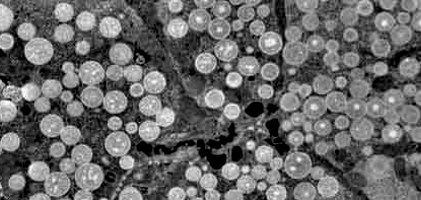

5.4 Fluorescence microscopy images containing Circulating Tumor Cells

In this subsection we demonstrate how our multiscale segmentation approach can be applied to the analysis of Circulating Tumor Cells (CTCs). Before presenting some experimental data sets we will first give a short introduction on CTCs, associated research questions and challenges for diagnosis and treatment of cancer patients.

Circulating Tumor Cells are cells that dissociate from a primary tumor and invade the blood stream. In recent literature it was shown that the number of CTCs present in the blood is associated with the survival chance of a patient and can be used to guide therapy of cancer patients. The elimination of CTCs indicates effective therapy whereas increase or failure to eliminate indicates a futile therapy. A challenge in the identification of CTCs is that they are very rare and therefore difficult to detect among other cells in the pool of blood cells. The gold standard for CTC enumeration is the CellSearch system and in prospective multicenter studies a threshold of 5 CTCs / 7.5 ml of blood was used to separate patients with metastatic disease into those with favorable and unfavorable prognosis [CBE+04, dBSM+08]. Currently all known CTC analysis tools are based on subjective morphological criteria and objects can be classified differently by different operators which results in different interpretation of the status of the patients. The low cell counts and subsequent statistical analyses further increases the chances of mistakes. The problem of subjectivity in the CTC analysis is currently addressed by the development of an open-source toolbox to automatically detect and classify CTCs in datasets from various machines and institutes. This project is part of a European consortium called CANCER-ID that aims at validating blood-based biomarkers and is funded by the European Union. One key component of this toolbox is the development of a (nearly) parameter-free segmentation algorithm which performs reliably and efficiently on multiple tumor cell datasets (see Figure 14).

Moreover, in recent studies [CDA+10] it was hypothesized that not only the definition used to classify objects as CTC predicted clinical outcome but also those objects that did not match the criteria of an intact cell. A schematic overview of different cell classes and their relative frequencies is shown in Figure 13. Here, green is a fluorescence marker indicating the presence of cytokeratin expressed in cancer cells but not on white blood cells and magenta is a fluorescence marker indicating the presence of DNA thus showing the nucleus of the cell. When comparing the green marker among the different CTC classes we observe that the signal clusters strongly vary in size (area) and therefore motivate the usage of our multiscale segmentation approach.

In Figure 14 (a), (d), (g) and (j) experimental data sets are shown. From the original image sets, consisting of three different fluorescent color channels, we extracted the tumor cell marker (green) and used those images as input for our multiscale segmentation approach. Although the difficulties vary between all images (inhomogeneous background, noise, cell clusters, mixture of size and intensity scales), we can process all images with our multiscale segmentation approach with the exact same parameters. This is essential for the development of a user-friendly (parameter-free) toolbox for CTC analysis. Note that the dim spots in image (d) are not cells but only pores of a filter used to collect cells (bright spots) and therefore it is not desired to segment them. The resulting spectral response functions for all four images are shown in Figure 14 (b), (e), (h) and (k) with a color coding corresponding to the coding used in the segmentation results in (c), (f), (i) and (l). The color coding of the response function shows that all objects which appear later in our segmentation and therefore belong to finer scales have a yellow to reddish color in the color-coded segmentation. The very large and intact cells are blue (with some small artifacts at the boundary) and smaller cells (or large fragments) are shown in light blue to green. We can nicely observe that the object colors cover the whole color scale range. For images that are more complex (e.g. (d) and (j)) also the spectral response function is more complex but the color-coded segmentation shows that nearly every object appears in one step and thereby has a clearly defined scale that we use as a feature in our classification approach. Here, we profit from the fact that not only Wulff shapes (perfectly circular objects) but also other eigenshapes appear in one step in our segmentation. Hence, this segmentation approach not only provides all contours automatically without any parameter adaptations but simultaneously also a simple classification of cells based on their size (scale resp. color/appearance time). This analysis can be applied to all color channels separately and be used together with more features in a subsequent automatic classification approach. The constants and can again simply be estimated a-priori from the data by a simple thresholding and averaging approach and are fixed throughout the iterative process.